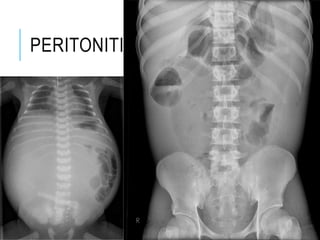

PERITONEUM

PERITONEAL CAVITY

PERITONITIS